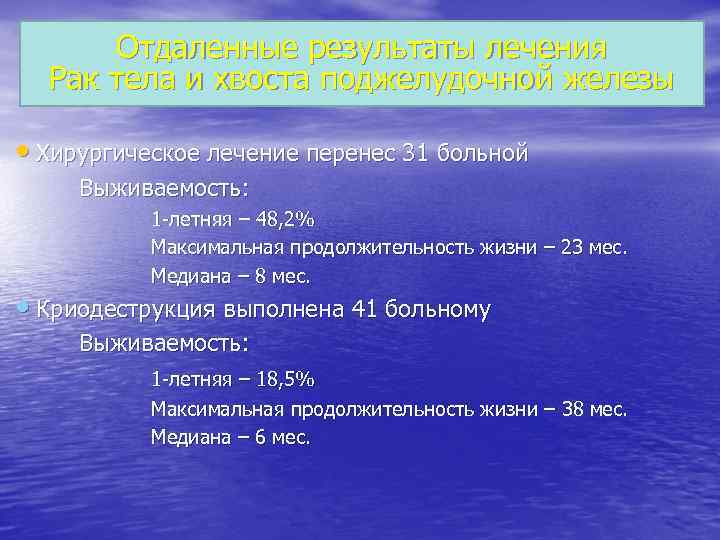

Отдаленные результаты лечения Рак тела и хвоста поджелудочной железы Хирургическое лечение перенес 31 больной Выживаемость: 1 -летняя – 48, 2% Максимальная продолжительность жизни – 23 мес. Медиана – 8 мес. Криодеструкция выполнена 41 больному Выживаемость: 1 -летняя – 18, 5% Максимальная продолжительность жизни – 38 мес. Медиана – 6 мес.